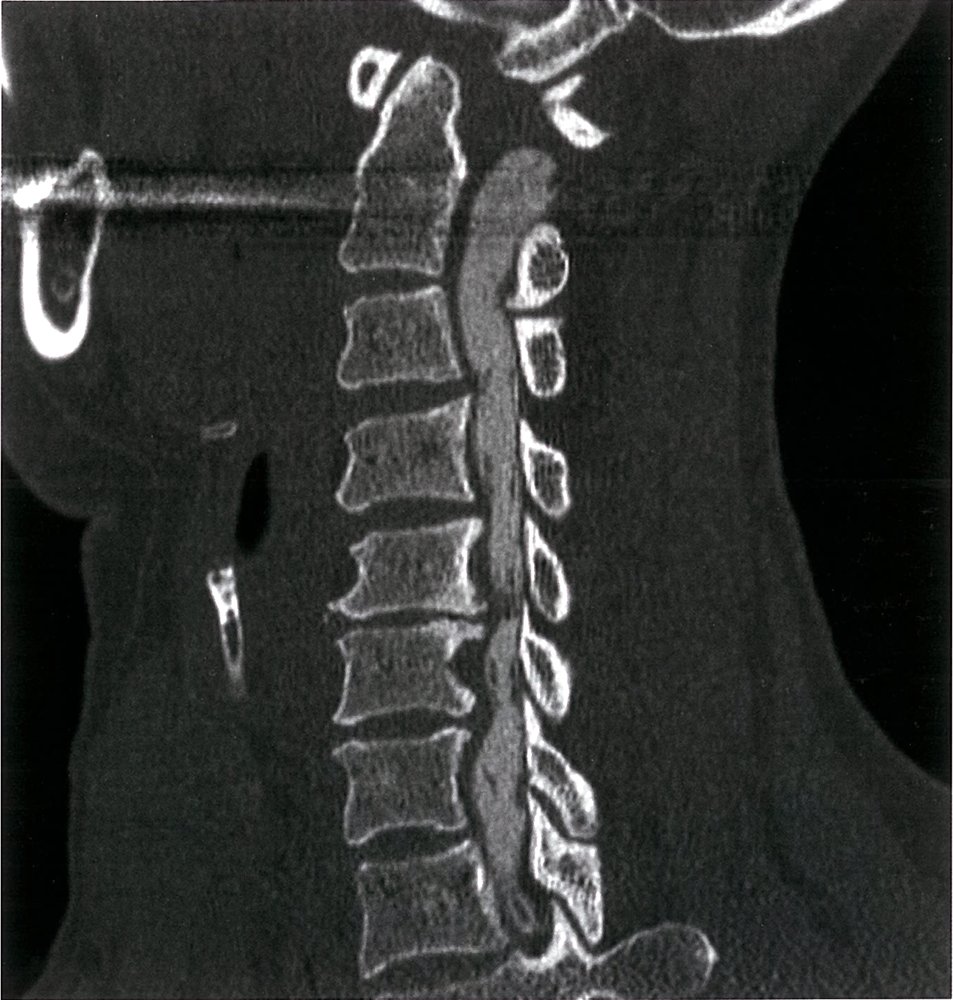

• Cervical x-ray : initial imaging test

• Reduced diameter of the spinal canal

• Degenerative changes of vertebral joints

• Osteophyte formation

• Narrowing of the disk space